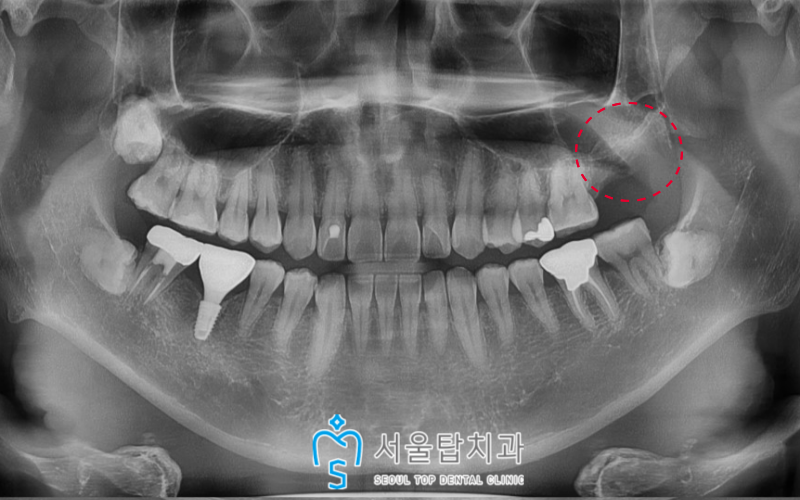

그리고 임플란트와 치조골이

단단하게 결합될 때까지

충분한 시간을 가진 뒤

골 유착이 잘 되었다고 확인되었을 때

최종 보철물까지 진행하여

임플란트를 성공적으로

마무리 해드렸답니다! 🦷